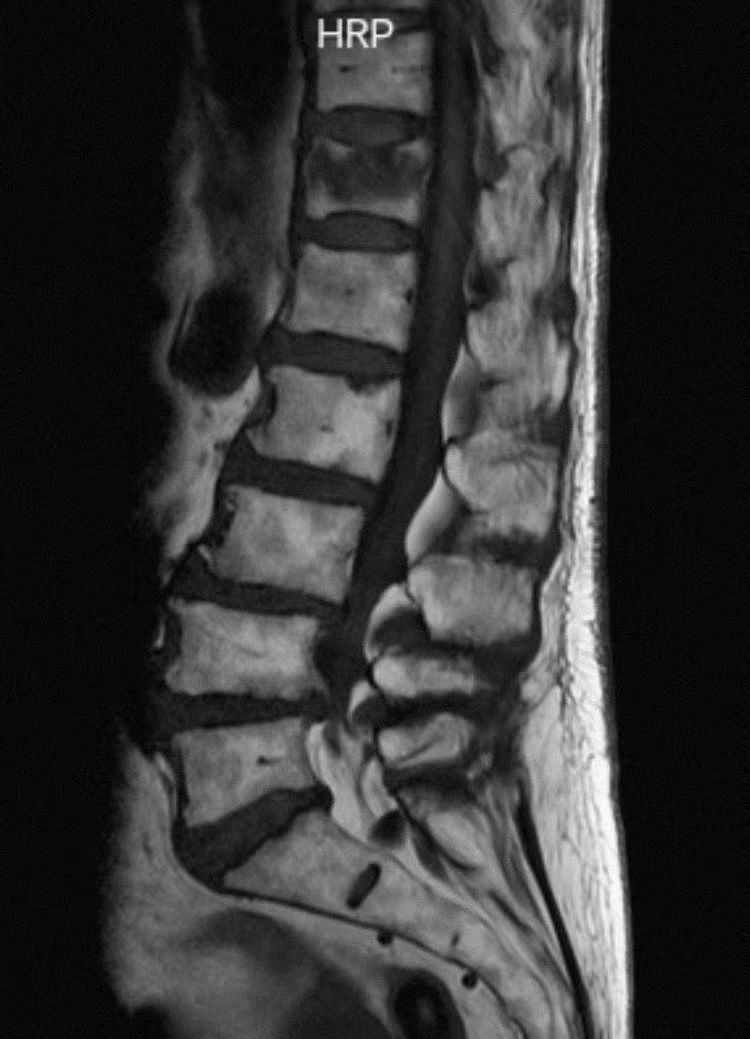

核磁共振T1像显示胸12压缩骨折。